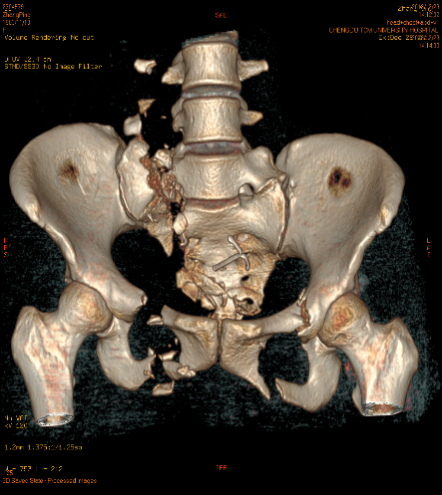

当时,张女士的右肾、胰头及体部均有损伤,还伴有盆腔积液和膀胱内积血。骨盆也有多处骨折:双侧骶翼、右侧耻骨上下支及多个骶、尾椎骨粉碎骨折,骶尾段滑脱;左侧耻骨上下支骨折;胸12椎体及附件;骨折腰1-5椎体右侧横突骨折、断端分离,右侧第6肋骨前段可疑骨折。

患者术前骨盆CT三维重建